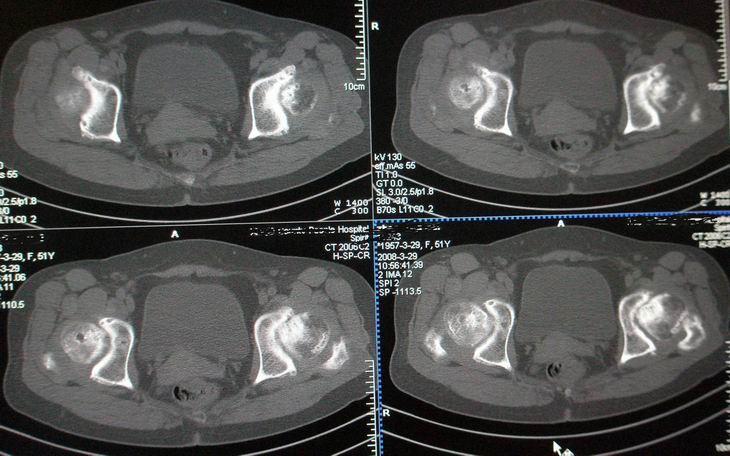

标题: CT12535:女,51岁.双髋痛多年,近加重,左腿难伸直. [打印本页]

标题: CT12535:女,51岁.双髋痛多年,近加重,左腿难伸直.

成人髋臼发育不良性骨关节病.是由于髋臼先天发育不良、髋臼角变大,部分股骨头位于髋臼以外,持重部位少,长期站立、负重造成髋臼退行性骨关节病,主要x线表现是:髋臼变浅平,髋臼角增大,ce角小于30度,髋关节骨性关节面增生硬化,关节间隙变窄,髋臼及股骨头可有囊变.但股骨头变形轻微,与股骨头坏死相比,预后好,可两三年变化不大,而股骨头坏死早期关节间隙不窄或增宽,等到间隙变窄时股骨头已明显变形.

(双侧股骨头变形明显,但坏死、囊变不明显)

此病人从未看过病.家穷,临床医生要她做了椎间盘,未发现明显异常.我免费给她做了双髋.是南方人.十几年前痛过,自行贴膏药,开始自我感觉还好后来不行.近两年痛加重.下登困难.左腿不能伸直.